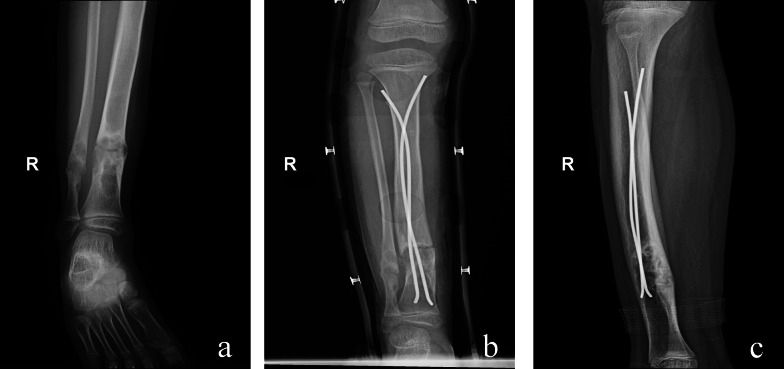

Materials and methods: This retrospective analysis included 28 patients (30 extremity) with severe pain, pathological fractures, angular deformities, or extensive cortical bone involvement. On the basis of the surgical approach, patients were divided into four groups: group 1, curettage, allograft, and plate fixation for six patients (six extremity); group 2, elastic stable intramedullary nailing fixation for six patients (six extremity); group 3, Fassier-Duval telescopic system fixation for eight patients (nine extremity); and group 4, interlocking intramedullary nail for eight patients (nine extremity).

Results: All patients achieved bony union and pain alleviation with no recurrence of deformities. The refracture rate during the follow-up was zero cases (0%; group 1) versus one (16.7%; group 2) versus zero (0%; group 3) versus zero cases (0% group 4) (p > 0.05). Instances of internal fixation loosening were zero cases (0%; group 1) versus zero (0%; group 2) versus five (55.6%; group 3) versus zero cases (0%; group 4) (p < 0.05). The musculoskeletal tumor society (MSTS) scores of the four groups were 27.5 (group 1) versus 27.7 (group 2) versus 26.3 (group 3) versus 28.7 (group 4) (p < 0.05).